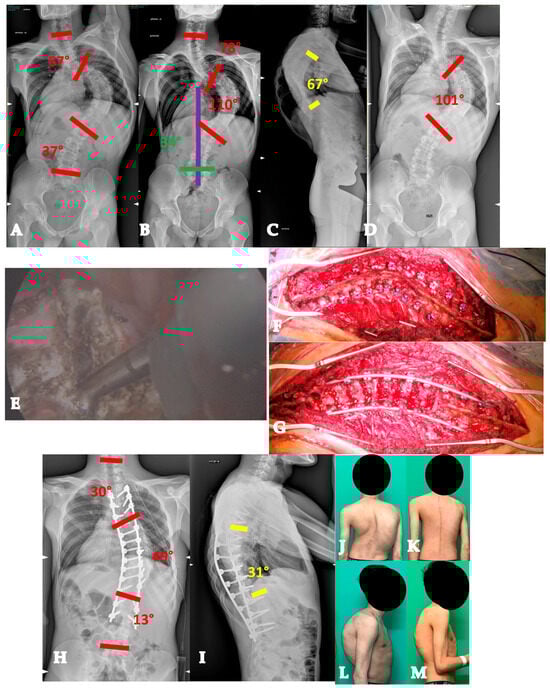

- AdIS 1B: 45–60 years old. These patients usually have a stiffer main curve, with the not infrequent presence of anterior column osteophytes, especially at the concave side. In this setting, combined corrective strategies based on posterior releases (Hi-PoAD [10]) can still achieve an optimal translation, but often, derotation potential is limited, with a possible residual of a partial rib hump (Figure 6).

- AdIS 1C: >60 years old. This is infrequent, since patients in this age group more commonly tend to lie in the AdIS 2 group. This group is burdened by an increased stiffness due to an even more frequent anterior column spontaneous fusion, resulting in a less powerful correction both in terms of translation and derotation, with a consequent smaller correction rate and more prominent residual rib hump. However, it must be considered that these patients more commonly present to surgeons because of pain rather than cosmetic concerns. In this view, pain generators should be carefully identified and adequately treated, performing foraminal and/or central decompressions and discectomies where appropriate (Figure 7).